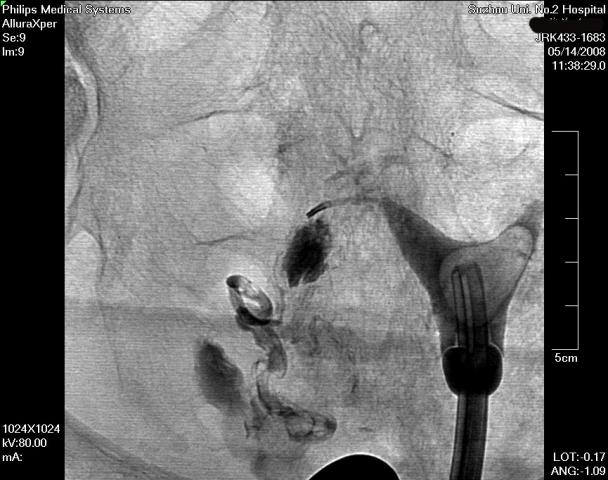

在清晰的DSA(数字减影血管造影机)的同步监测,采用同轴导管系统,进行输卵管选择性造影和再通术,主要适用于输卵管阻塞于间质部及狭部的不孕症患者,各段输卵管阻塞均可行选择性输卵管造影、通液。主要采用导管扩张术,插入导管导丝,利用导管导丝的推进扩张分离作用和造影剂的冲击力等,使输卵管疏通至伞端。手术安全高效,痛苦小,无需住院,复通率及术后妊娠率均较高。(见图1术前HSG宫腔形态正常,双侧输卵管不显影、图2左侧输卵管顺利通过导丝后造影剂通过畅、图3右侧输卵管通过导丝后畅)